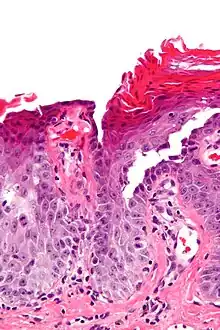

Micrograph of transient acantholytic dermatosis, showing subcorneal separation and acantholysis. H&E stain.

Grover's disease (GD) is a polymorphic, pruritic, papulovesicular dermatosis characterized histologically by acantholysis[2]:529 with or without dyskeratosis.[3] Once confirmed, most cases of Grover's disease last six to twelve months, which is why it was originally called "transient". However it may last much longer. Nevertheless, it is not to be confused with relapsing linear acantholytic dermatosis.

Grover's may be suspected by its appearance, but since it has such a characteristic appearance under the microscope a shave skin or punch biopsy is often performed.